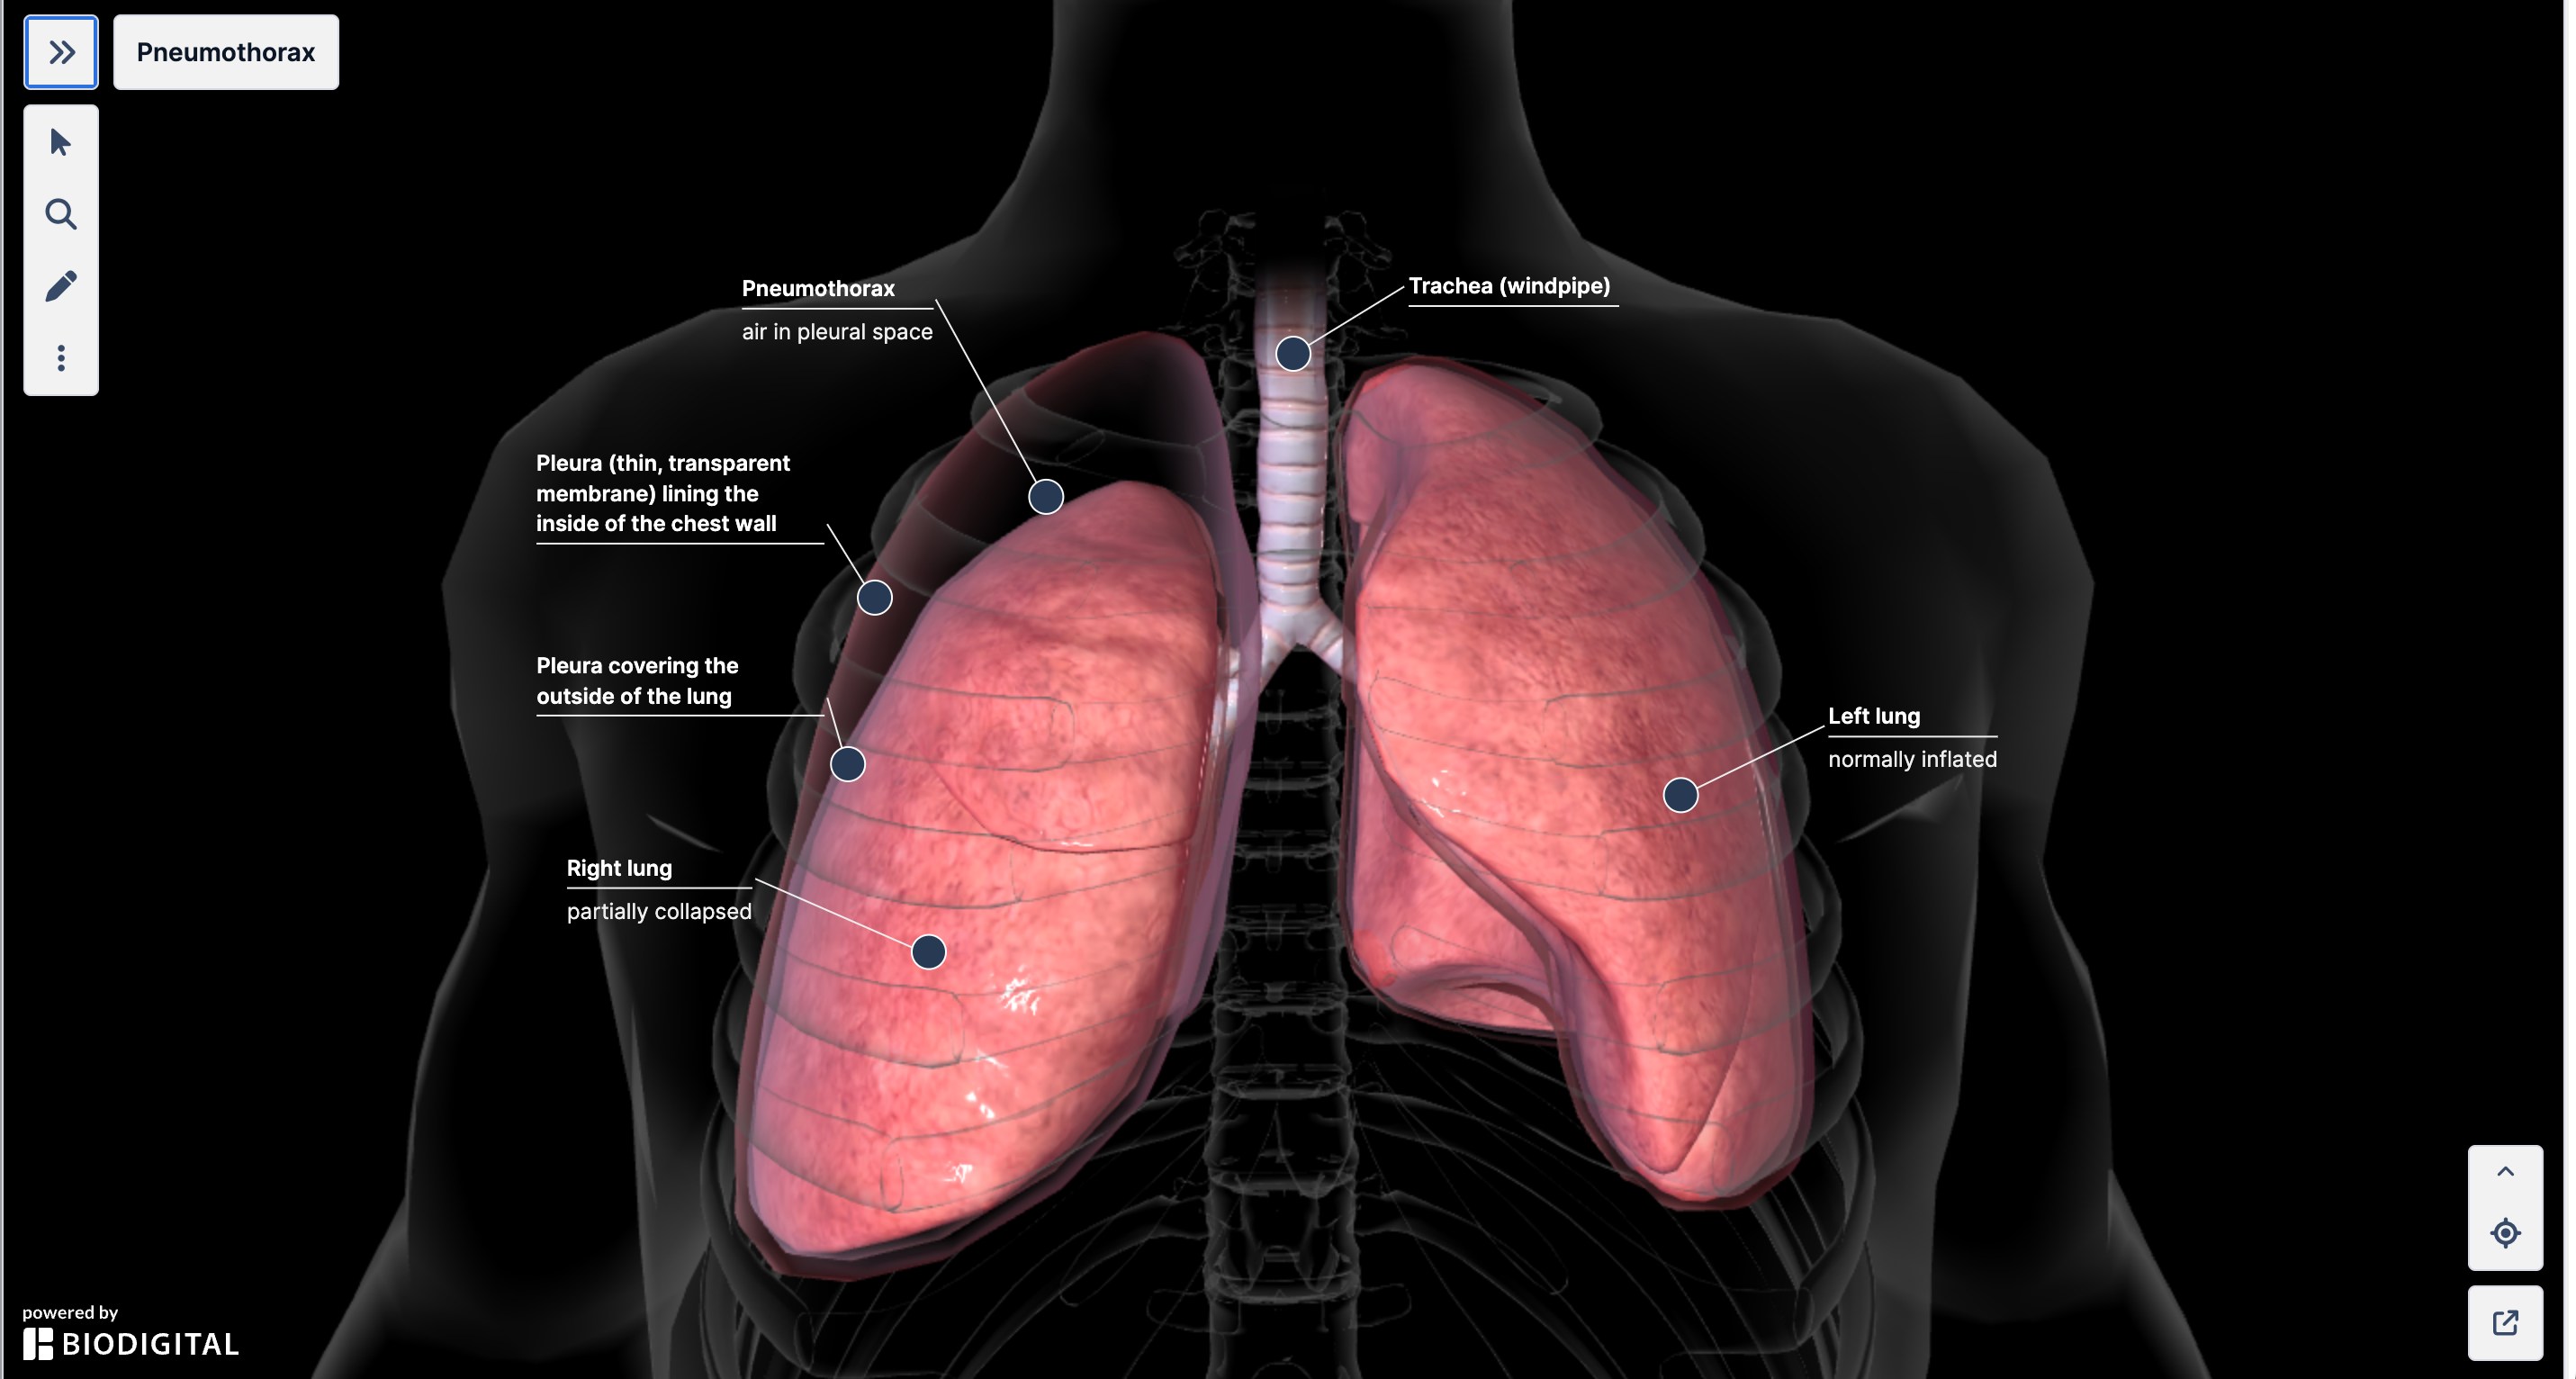

Class 10 - Biology

The human lungs.